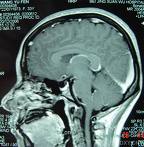

鞍膈

即颅底的

硬脑膜

覆盖在

垂体窝

上方的水平位的膈板。呈长方形,其表面下凹或平直。鞍膈中央的小孔称膈孔,有

垂体柄

通过。